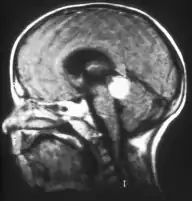

Inherited forms of retinoblastomas are more likely to be bilateral. In addition, inherited uni- or bilateral retinoblastomas may be associated with pineoblastoma and other malignant midline supratentorial primitive neuroectodermal tumors (PNETs) with a dismal outcome; retinoblastoma concurrent with a PNET is known as trilateral retinoblastoma.[15] A 2014 meta-analysis showed that 5-year survival of trilateral retinoblastoma increased from 6% before 1995 to 57% by 2014, attributed to early detection and improved chemotherapy.[16]

In about two-thirds of cases,[27] only one eye is affected (unilateral retinoblastoma); in the other third, tumors develop in both eyes (bilateral retinoblastoma). The number and size of tumors on each eye may vary. In certain cases, the pineal gland or the suprasellar or parasellar region (or in very rare cases other midline intracranial locations) is also affected (trilateral retinoblastoma). The position, size, and quantity of tumors are considered when choosing the type of treatment for the disease.

Aspect of trilateral retinoblastoma on MRI